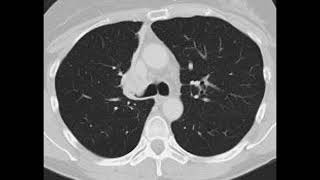

FRCR 2B RS Case 06